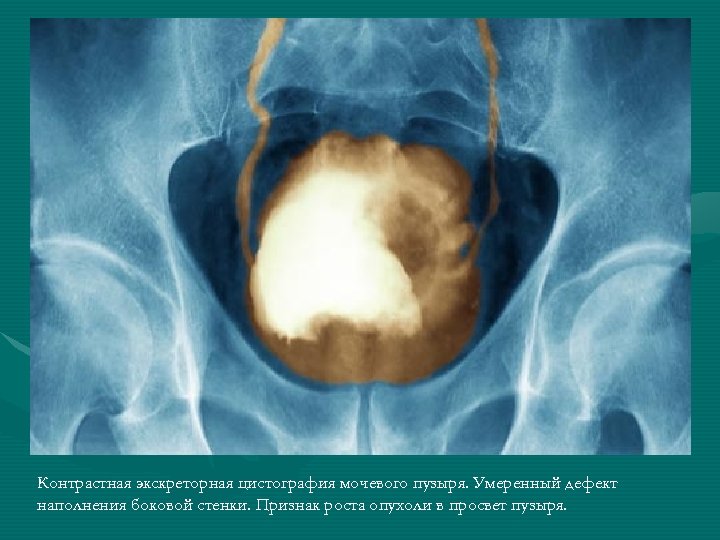

• • • Диагностика Стандартным методом диагностики опухолей есть цистоскопия и биопсия опухоли. Цистоскопия Биопсия ткани опухоли мочевого пузыря Цитологическое исследование осадка мочи Сложные методы диагностики (комп’ютерная томография, УЗИ) Процедура проведения цистоскопии

Контрастная экскреторная цистография мочевого пузыря. Умеренный дефект наполнения боковой стенки. Признак роста опухоли в просвет пузыря.